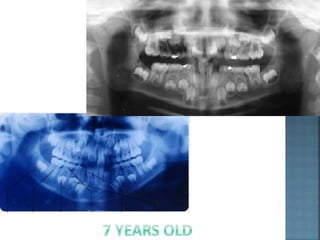

Physiological spacing (ugly duckling) stage. A transient

anterior open bite can be associated with eruption of the

incisors as they approach the occlusal plane and this

invariably improves with time. The maxillary central

incisors can also be quite distally inclined when they first

erupt, which produces a midline diastema between them.

This physiological spacing or ‘ugly duckling’ stage is

thought to be due to the combined effect of the maxillary

incisor apices being initially quite close together in the

anterior maxilla as the incisors erupt and lateral pressure

from the erupting maxillary lateral incisors and canines

7 year 9 year 14 year

As these teeth erupt this pressure is transferred

from the apical region of the maxillary incisors

more coronally, improving their inclination and

usually closing the diastema.